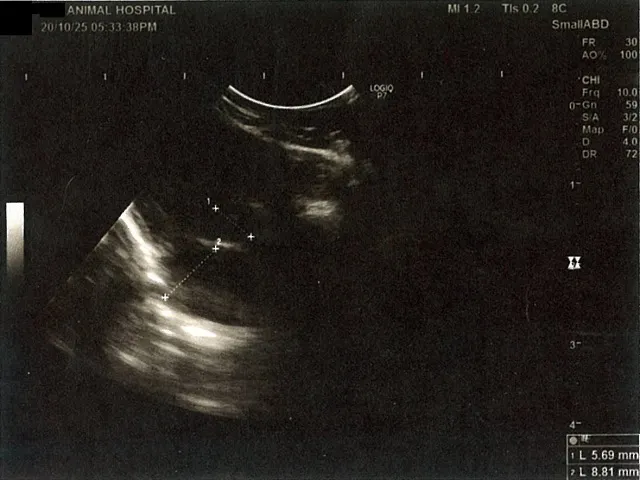

《心臓周りの胸部以外の全ての腹部で腹水がみられるとの診断です》

大網という部分で内臓を包む膜のようなものです。その周りに腹水が溜まっています。

左腎臓周りに腹水が確認できるエコー写真